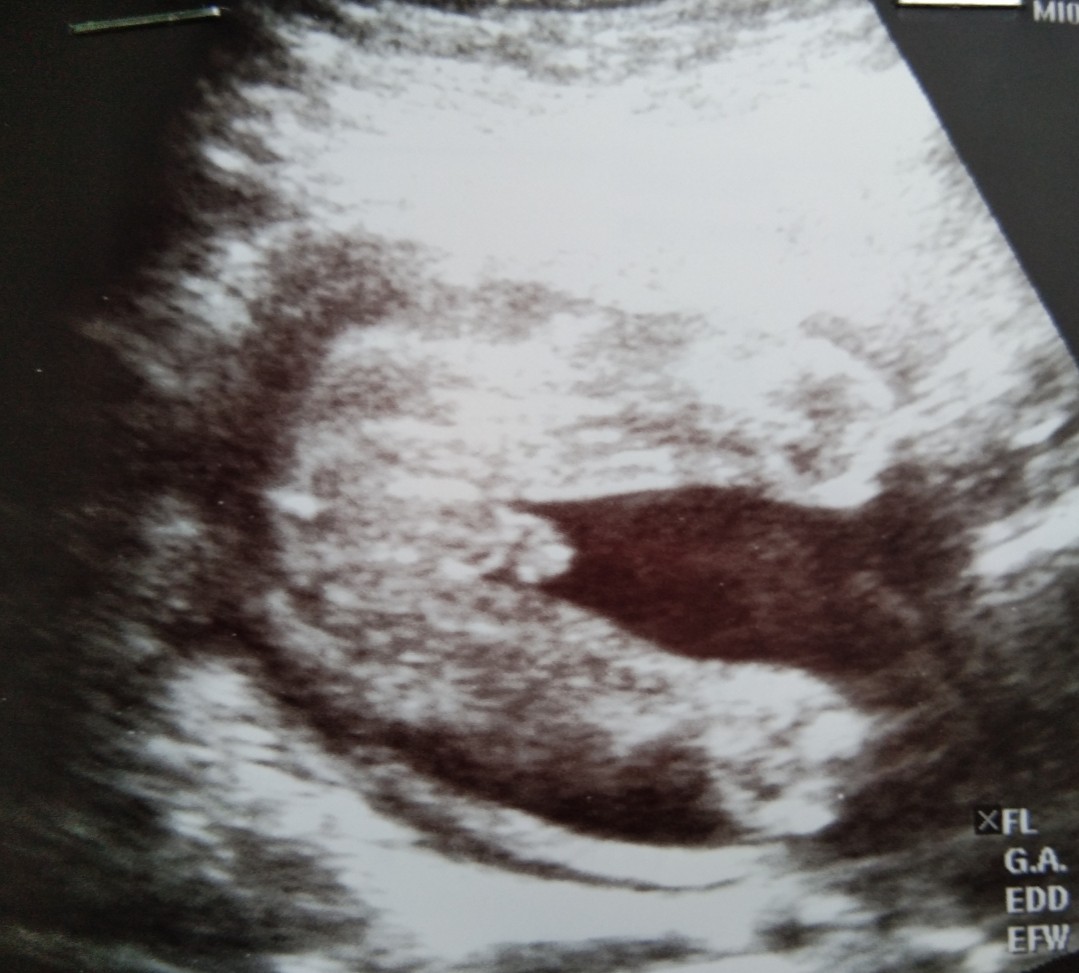

ไช่ค่ะ เเม่บ้านนี้ดูยังไงก็ดูไม่ออกเลยค่ะเเม่ แต่หมอบอกได้ลูกสาวค่ะ

ดูให้น่อยจ้า ช. ญ.